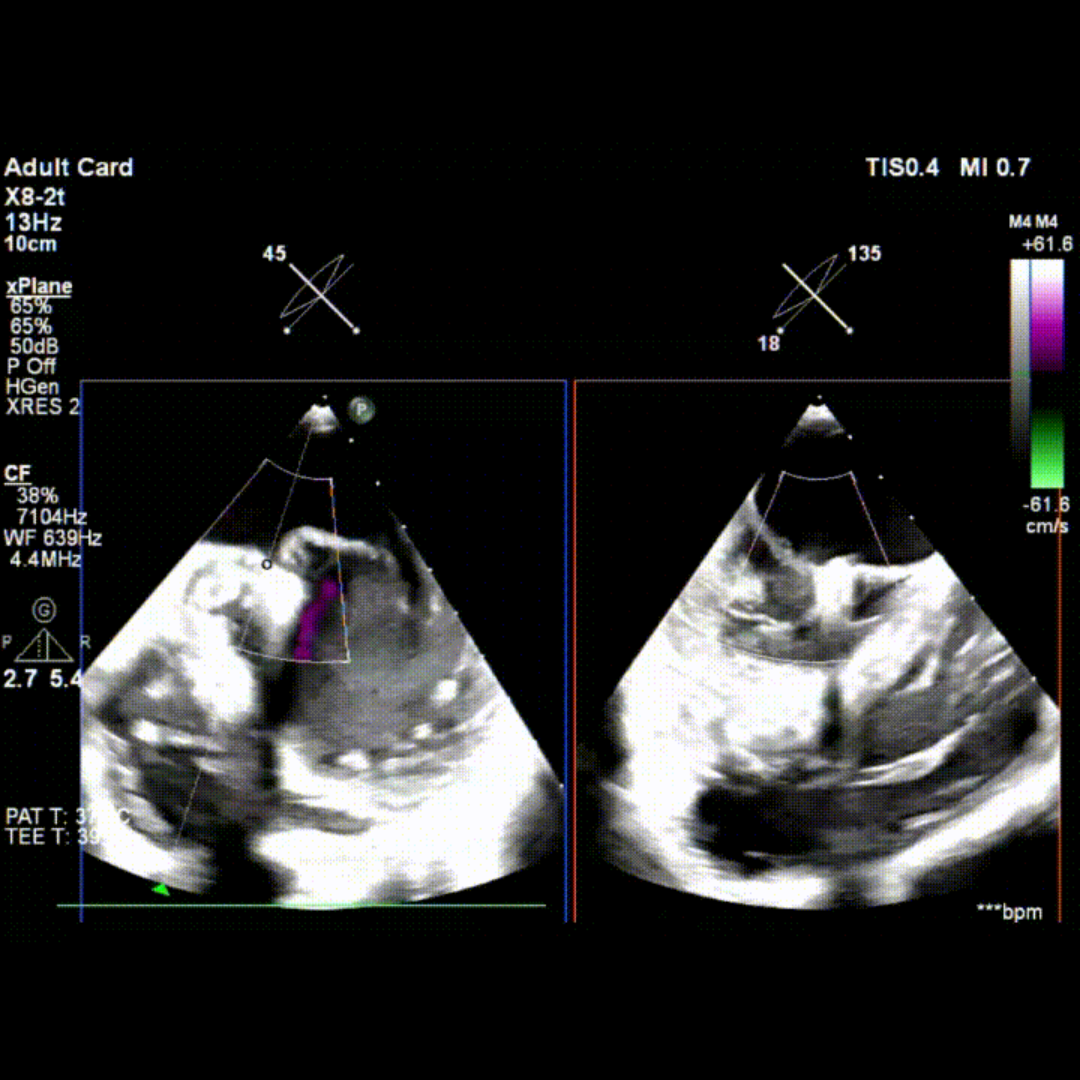

术中TEE影像

李伟教授强调,TA-TEER术前评估必须依托临床、影像、心外等多学科的协作。术前需完成经胸及经食道标准切面成像,并进行详尽规划,评估MR分型、病因、严重程度及左心解剖结构与功能。同时,他详细解析了适合TA-TEER的解剖结构类型及相关测量方法。李伟教授重点讲解了术中成像要点,包括心尖穿刺点与夹子释放的实时超声引导。他总结道:手术成功的关键“五分在操作技术,五分在策略制定”。